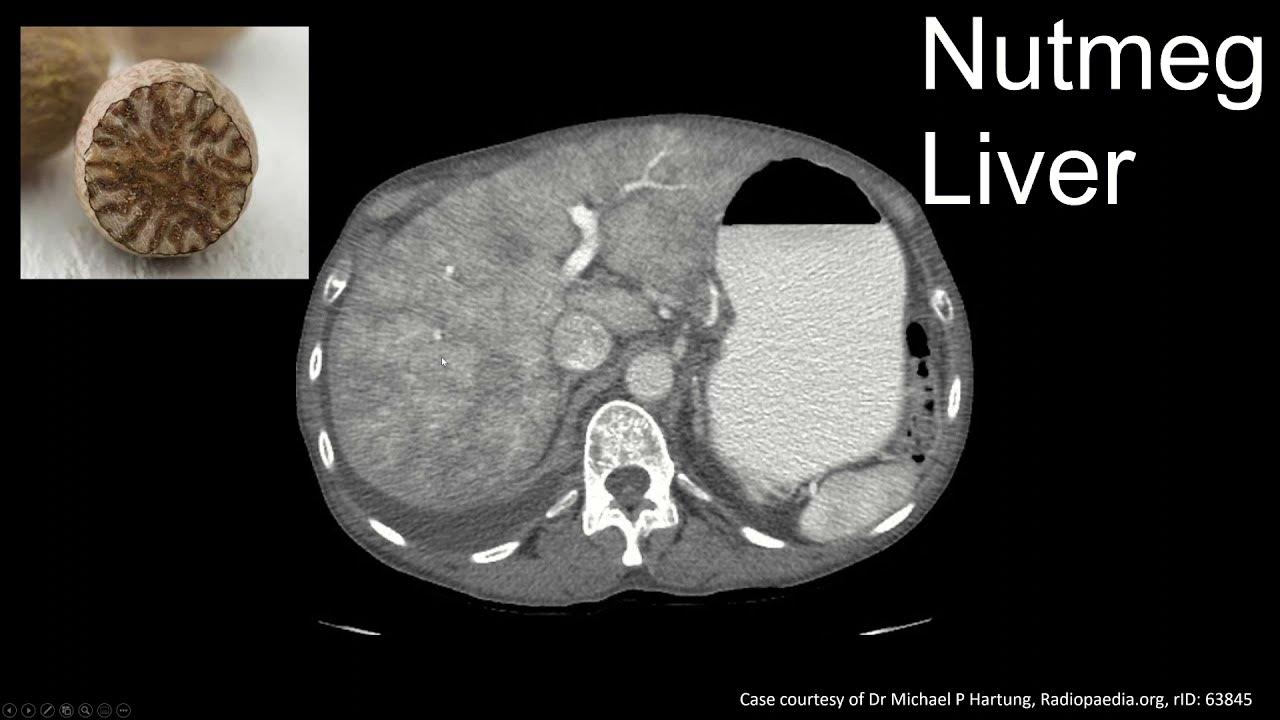

Nutmeg Liver Is Indicative Of . Nutmeg liver is most frequently seen in right heart failure, and this diagnosis may be suggested by ancillary imaging findings such. Right middle lung lobe atelectatic changes. Nutmeg liver refers to the mottled appearance of the liver as a result of hepatic venous congestion. Nutmeg liver refers to the mottled appearance of the liver as a result of hepatic venous congestion. Highlights the pathophysiology, microscopic findings and associated hepatic diseases with common structural changes, patterns of cell damage and necrosis, intracellular. A nutmeg liver appearance is due to a perfusion abnormality of the liver usually as result of hepatic venous congestion. Radiologically, it is most appreciable on.

A nutmeg liver appearance is due to a perfusion abnormality of the liver usually as result of hepatic venous congestion. Radiologically, it is most appreciable on. Right middle lung lobe atelectatic changes. Highlights the pathophysiology, microscopic findings and associated hepatic diseases with common structural changes, patterns of cell damage and necrosis, intracellular. Nutmeg liver refers to the mottled appearance of the liver as a result of hepatic venous congestion. Nutmeg liver refers to the mottled appearance of the liver as a result of hepatic venous congestion. Nutmeg liver is most frequently seen in right heart failure, and this diagnosis may be suggested by ancillary imaging findings such.